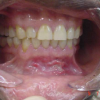

Krooniline parodontiit

Krooniline parodontiit on mikroobide poolt põhjustatud hammaste tugikudede põletik, mille tulemusena tekib progresseeruv alveolaarluu (nähtav röntgenograamil) ja periodontaalligamendi destruktsioon, igemetaskute moodustumine, igeme retsessioon või mõlemad kahjustused kombineeritult. Krooniline parodontiit on...